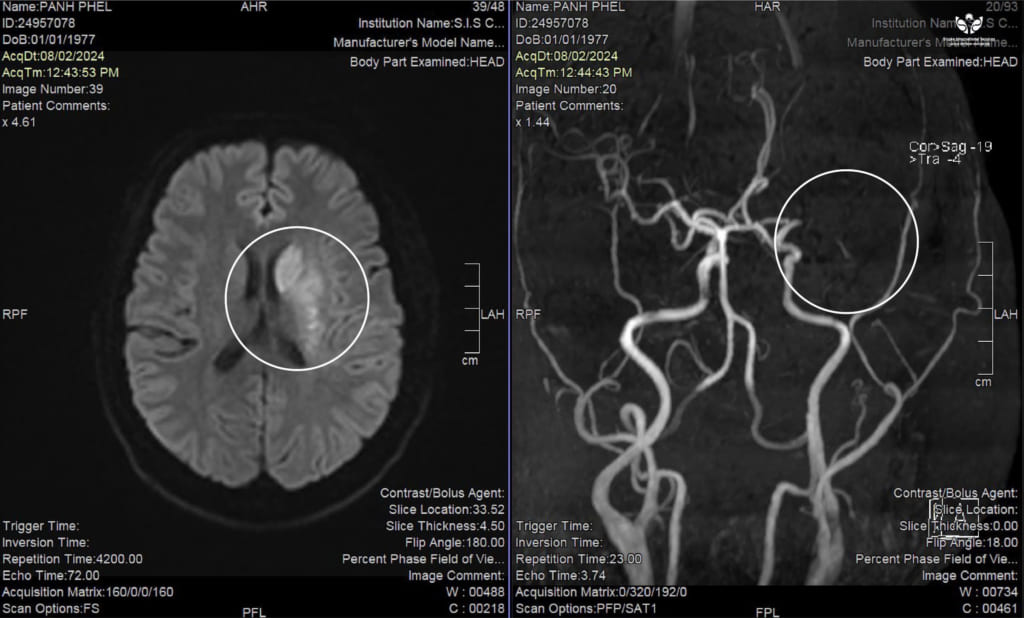

Được biết, bệnh nhân P.P nhập viện trong tình trạng liệt tay chân phải, không nói được, tiếp xúc chậm. Sau khi có kết quả chụp MRI não, bác sĩ chẩn đoán bệnh nhân bị đột quỵ nhồi máu não. Bác sĩ tư vấn với người nhà cần phải can thiệp nhanh chóng cho bệnh nhân.

Là người trực tiếp can thiệp và theo dõi điều trị cho bệnh nhân P.P, BS Dương Hoàng Linh – Đơn vị DSA cho biết: “Bệnh nhân được cấp cứu, thăm khám tích cực và đưa đi chụp MRI não. Kết quả chẩn đoán bệnh nhân bị đột quỵ nhồi máu não do tắc 1 động mạch lớn trên não. Nếu không can thiệp kịp thời thì tỉ lệ tử vong và tàn phế có thể lên đến 60-70%. Chúng tôi tư vấn chi tiết tình trạng bệnh nhân và được sự đồng ý của gia đình. Ngay sau đó, bệnh nhân đã được đưa lên phòng DSA để tiến hành can thiệp.

Ekip đã tiến hành can thiệp hút huyết khối, nhưng sau đó không tái thông được. Chúng tôi phải dùng đến phương pháp cuối cùng là nong mạch máu cho bệnh nhân mới tái thông lại được. Sau can thiệp, bệnh nhân phục hồi tốt. Đến ngày xuất viện bệnh nhân đã tỉnh táo, ăn uống được, đã nói lại được nhưng chưa linh hoạt. Về sức tay chân của bệnh nhân đã có thể cử động nhẹ.